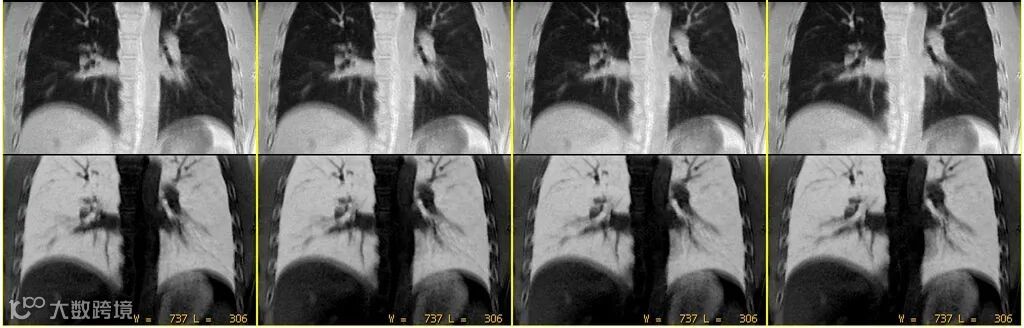

其原始对比度主要反映组织的质子密度和T1弛豫特性。上图△,FA=1°,体素0.8*0.8*0.8mm。

上图△,肺部成像。成像FA =2°,体素1.0*1.0*1.0mm。

上图△,肋骨成像。成像FA =2°,体素1.0*1.0*1.0mm。